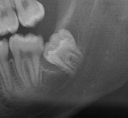

Figure 2. Fully developed #32 with increased risk for nerve injury.

• Early removal is better. Younger patients heal faster and easier. When roots are not fully developed, the chance of inferior alveolar nerve injury decreases. Complications and morbidity of surgery increase with older age.2